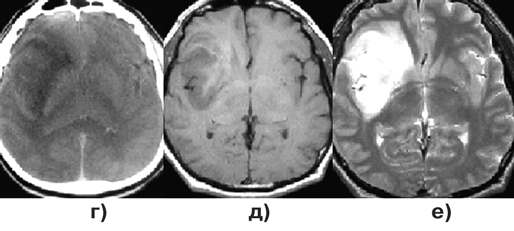

Если удаление опухоли сопряжено с риском нарастания неврологической симптоматики, может быть показано проведение только стереотаксической биопсии. При верификации глиомы низкой степени злокачественности возможно проведение курса дистанционной гамма-терапии без удаления опухоли (рис. 2а, б). В отдельных случаях оправдано динамическое наблюдение за больным (рис. 2в, г).

Рисунок 2. Фибриллярная астроцитома:

а — фибриллярная астроцитома левой лобно— височной области (КТ с контрастным усилением до лучевой терапии); б — фибриллярная астроцитома левой лобно-височной области (КТ с контрастным усилением через 5 лет после лучевой терапии); в — фибриллярная астроцитома левой лобно-височной области (МРТ, Т1-взвешенные изображения, до стереотаксической биопсии); г — фибриллярная астроцитома левой лобно-височной области (МРТ, Т1-взвешенные изображения, через 4 года после стереотаксической биопсии)